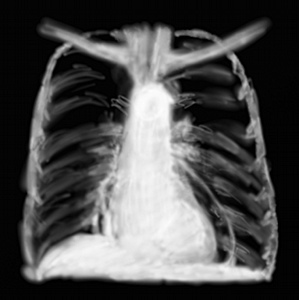

RP pneumopéritoine

Ce n’est absolument pas une urgence thoracique mais on la voit très bien sur une RP ! Il n’y a pas d’utilité d’un cliché de coupoles quand on fait un ASP abdomen sans préparation, et si on suspecte une pathologie à sanction chirurgicale (cholécystite aiguë, volvulus intestinal, colite ischémique, appendicite perforée), une RP est souvent demandée dans le bilan, autant la faire au moment du diagnostic (indépendamment des critiques qui sont faites sur la faible utilité de l’ASP en urgence).

Hyperclartés en croissant, poches d’air sous les deux coupoles diaphragmatiques par issue d’air gastrique, intestinal, colique ou restant de pneumopéritoine de coelioscopie; ou parfois si l’issue d’air est énorme, grosses bulles d’air qui voilent les coupoles.

Bref ça crève les yeux.

A ne pas confonde avec une dilatation gastrique considérable comme dans la dilatation aiguë de l’estomac, ou de l’air à l’angle colique droit ou gauche (syndrome de Chilaiditi).